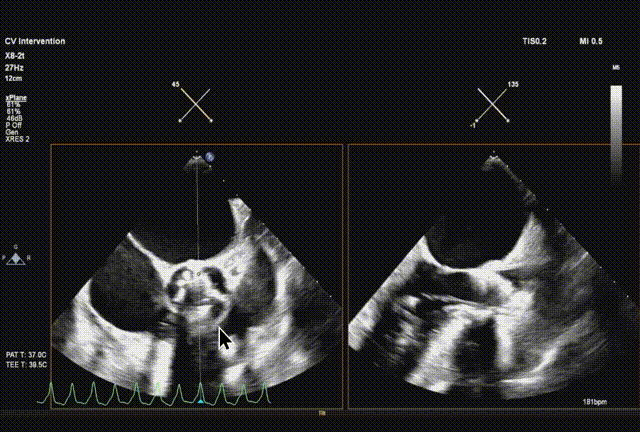

球囊预扩

输送系统顺利跨瓣

瓣膜初始释放到喇叭状形态并定位植入深度

采样线扫到无窦,180起搏,长轴视图下快速释放到工作位

超声从左至右,最后无冠窦侧评估深度合适

起搏下完全释放瓣膜